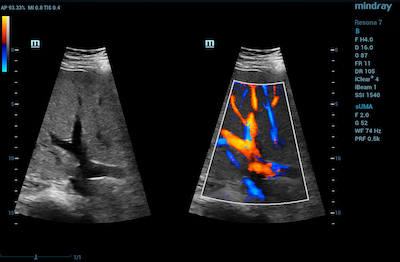

- Ultra Micro Angiography (UMA) is an innovative method of visualizing low-velocity micro-vascular flow states. UMA compensates for the limitations of traditional flow modes in detecting slow flow. It allows for visualization of the supply vessels surrounding diseased tissues, further enhancing diagnostic capabilities for lesion detection and characterization.

- Color UMA – UMA with a traditional color map overlay for improved sensitivity

- Power UMA – UMA with Power Doppler sensitivity, also available in bidirectional mode

- Subtraction UMA – UMA combined with tissue subtraction for enhanced evaluation of vessels separate from grayscale imaging

Color Ultra Micro Angiography of Hepatic Vasculature

Subtraction Ultra Micro Angiography of Renal Profusion